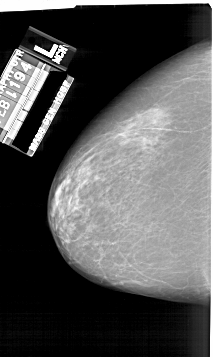

A_1925_1.RIGHT_CC

RIGHT_CC LINES 5431 PIXELS_PER_LINE 3451 BITS_PER_PIXEL 12 RESOLUTION 43.5 OVERLAY